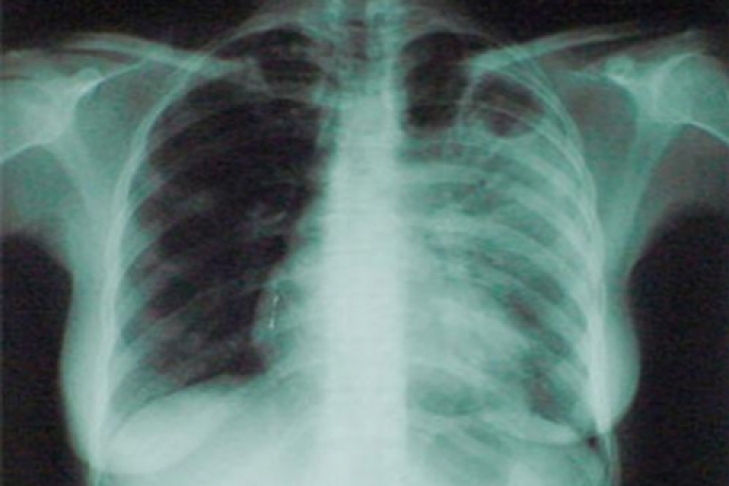

Рентген бесполезен при выявлении рака легких

Аппарат «не видит» рак на ранних стадиях

Обычный рентген не способен выявить рак легких на ранних стадиях, - выяснили американские ученые. Как эффективную альтернативу они предлагают использовать компьютерную томографию легких для диагностики возможного заболевания.

Долгосрочный эксперимент показал, что благодаря использованию компьютерного томографа удалось снизить смертность от рака легких на 20%, по сравнению с теми данными, которые показывала классическая радиография.